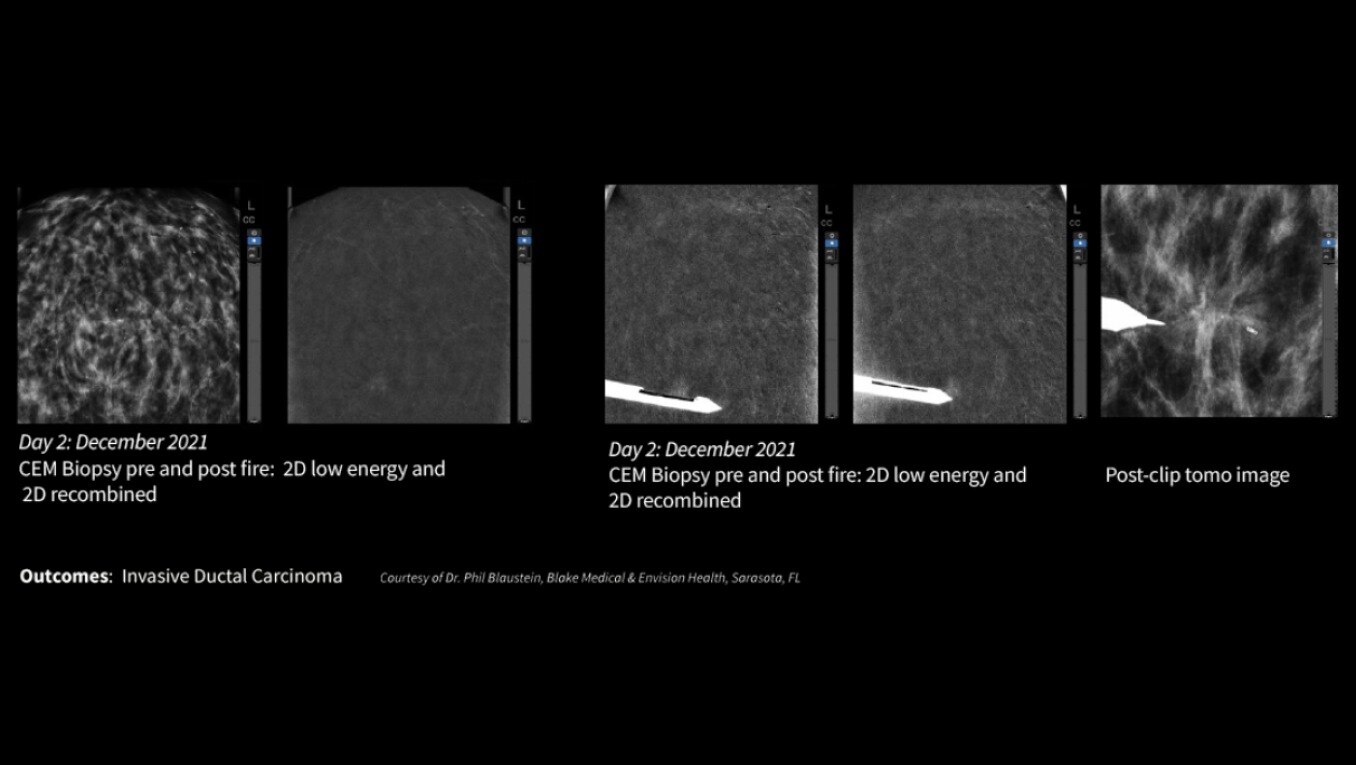

Serena Bright™

Contrast-guided biopsy solution

Utilizes contrast-spectral mammography to clearly target and biopsy lesions without leaving the mammography suite.